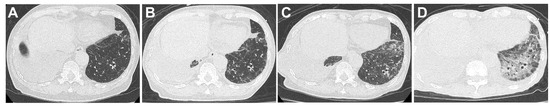

(1) Background: Helminth infections are a widespread global health concern, with Ascaris and taeniasis representing two of the most prevalent infestations. Traditional diagnostic methods, such as egg-based microscopy, are fraught with challenges, inc...